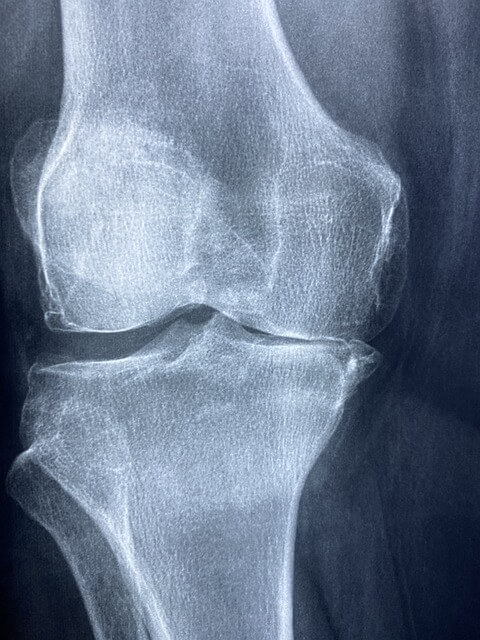

무릎은 우리 몸에서 가장 큰 관절로, 일상생활의 움직임에 필수적인 역할을 합니다. 그러나 무릎 관절은 나이가 들수록 손상되기 쉽고, 특히 무릎 연골의 손상은 많은 사람들에게 큰 불편을 초래합니다. 무릎 연골은 충격을 흡수하고 관절의 부드러운 움직임을 돕는 중요한 역할을 하지만, 다양한 원인으로 인해 손상될 수 있습니다. 이런 경우 많은 이들이 선택하는 것이 바로 무릎 연골주사입니다. 오늘은 무릎 연골주사가 무엇인지, 그 효과와 지속 기간, 맞는 시기, 무릎 연골주사를 맞을 수 있는 경우와 그렇지 않은 경우, 그리고 부작용까지 꼼꼼히 살펴보겠습니다.

무릎 연골주사는 무릎 관절 내에 연골을 보호하고 재생을 돕는 약물을 주입하는 치료법입니다. 주로 사용되는 주사에는 히알루론산, 스테로이드, PRP(혈소판 풍부 혈장) 등이 있으며, 각각의 주사제는 특정한 목적과 효과를 가지고 있습니다.